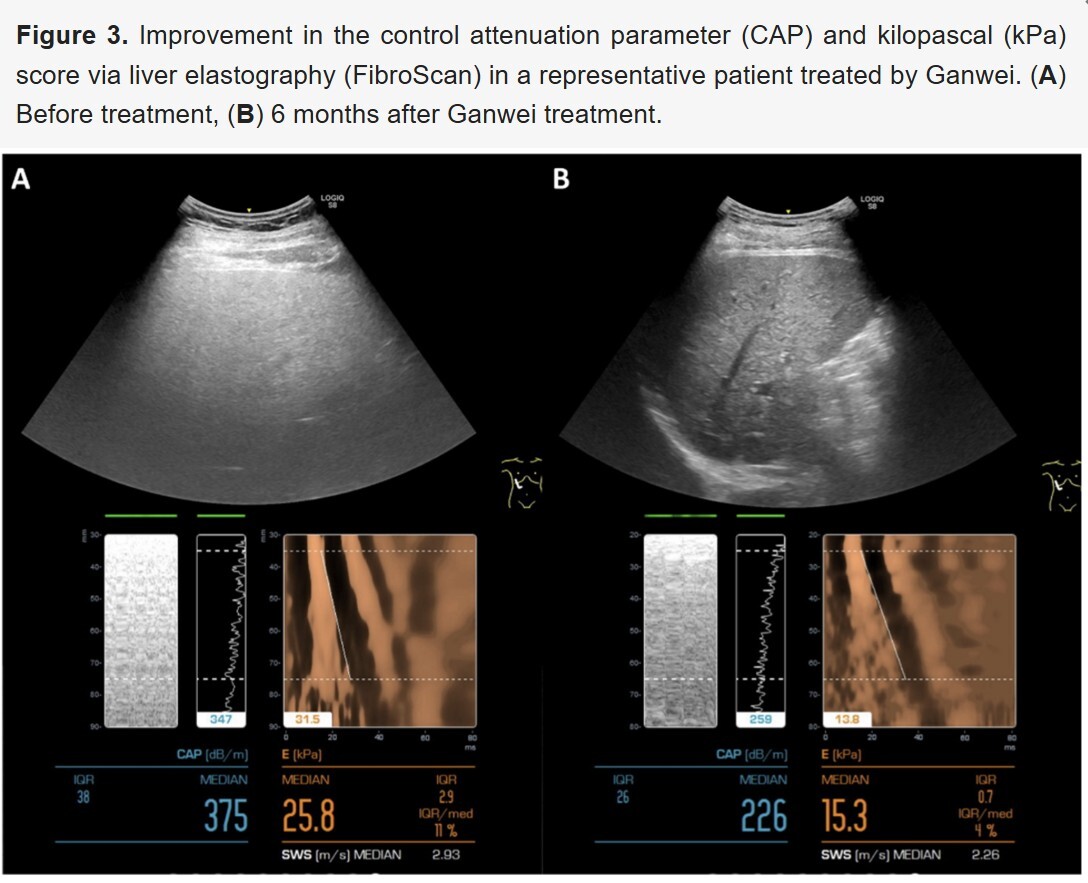

Our research team has dedicated immense effort to produce this ground breaking study.

We invite you to explore our findings.

https://www.mdpi.com/1422-0067/27/5/2411